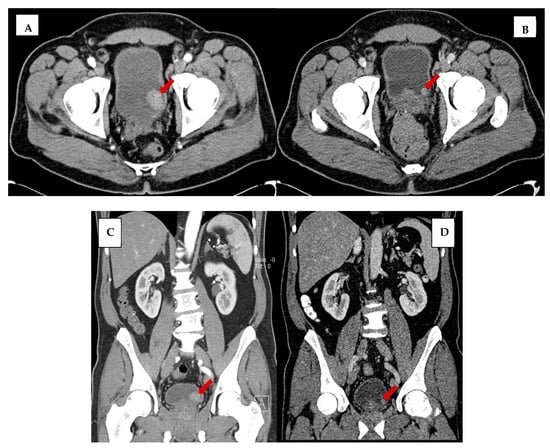

3. Results